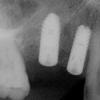

Ilyen a digitális röntgen és képelemző rendszer. Ennek egyik előnye a hagyományos röntgenhez képest, 90%-kal kisebb sugárterhelés, amely még nagyobb felvételszám vagy kismamák esetében sem jelent a szervezet számára megterhelést. Másrészt, a szokásos röntgenfilmnél akár 50-100-szor nagyobb képátmérőnek köszönhetően a legapróbb részletek sem maradnak észrevétlenek, ami még pontosabb diagnózist eredményez. A felvételek számítógépes elemezésével alaposabb kezelési tervet lehet készíteni, sőt, amint az a képeken is látható, az ellátás modellezésére és akár menet közben történő ellenőrzésére is lehetőség van.